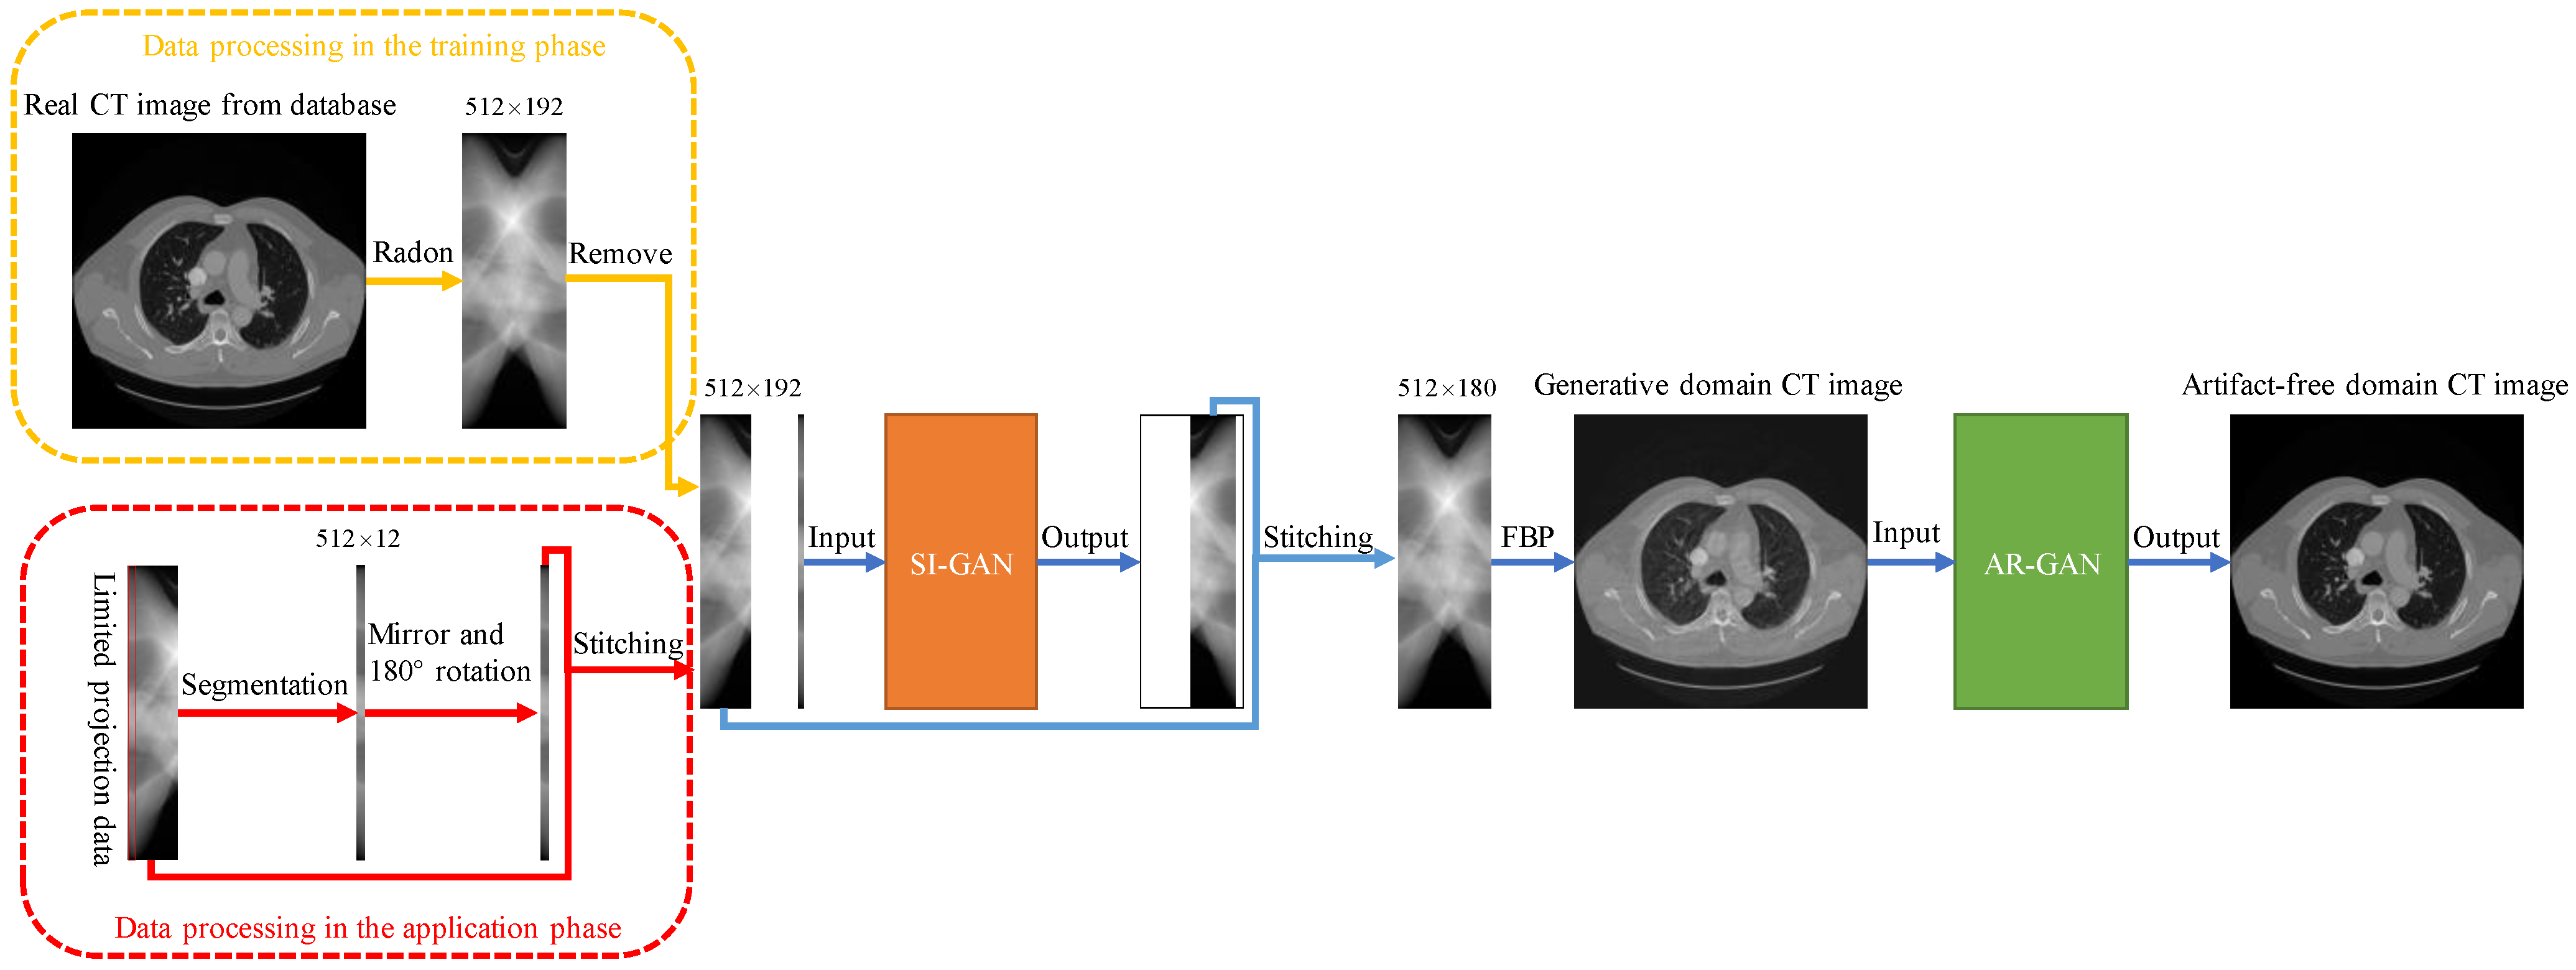

2.1. Sinogram Inpainting Generative Adversarial Network (SI-GAN)

2.2. Artifact Removal Generative Adversarial Network (AR-GAN)